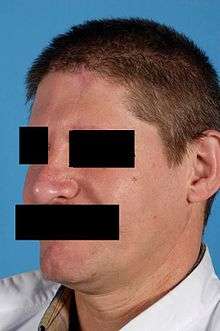

Results

The goal of nasal reconstruction is to look as normal as possible after reconstruction.[7] The results of nasal reconstruction using the paramedian forehead flap are quite good, although some patients report functional difficulties. Airway passage difficulties, mucosal crusts, dry mucosa, and difficulties with smelling are uncommon.[5] A minority of the patients reported snoring more often or having a spontaneous nose bleed more often.[5] Difficulties with phonation are not likely to occur. The majority of patients are satisfied with function of the nose after reconstruction.[5]

Ideally, standardized semistructered interviews are used to assess aesthetic outcome after nasal reconstruction. Studies using these interviews showed that generally patients are very satisfied with the result although they reported aggravating of their nasal appearance compared to before surgery.[5] Patients were especially satisfied with flap color match and shape of the nasal tip.[5] Remarkably, patients scored subjective aesthetic outcome significantly higher compared to a professional panel.[8]